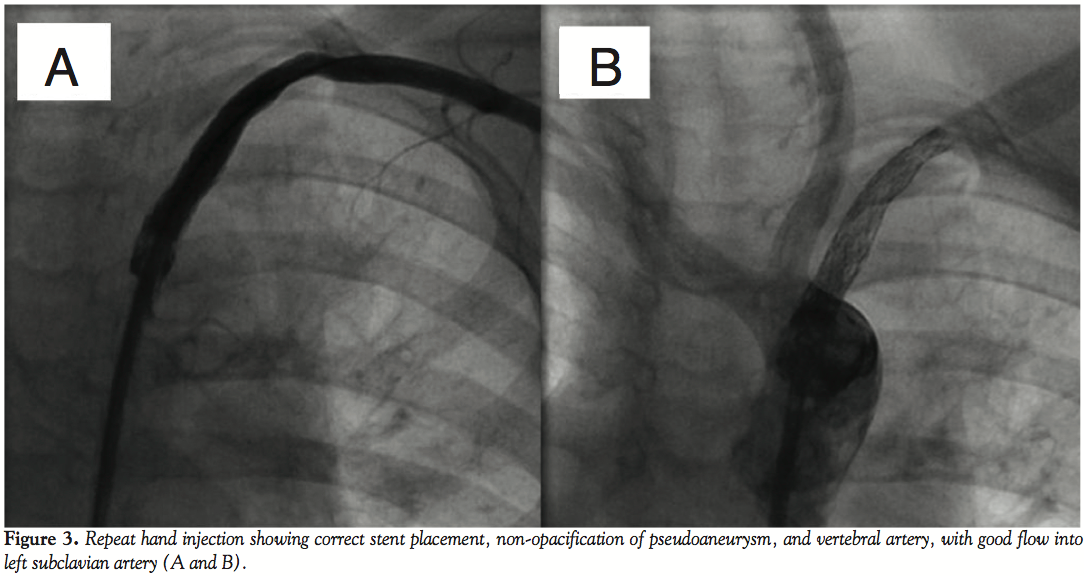

11 mm) without any distortion. A 5 Fr multipurpose catheter was introduced through right femoral artery to aorta to left subclavian artery (LSA). Hand injection in anteroposterior view showed corrugated and irregular luminal surface of BT shunt with pseudoaneurysm at the origin of LSA (Figure 1, Video 1). We performed a 4-vessel angiogram to ascertain the patency of the carotid and vertebral arteries. We introduced a 0.035” extrastiff wire through the multipurpose catheter, which was lodged in the LSA, and tracked a 7 Fr sheath over it. A 6 mm x 16 mm Advanta V12 balloon expandable covered stent (Atrium Medical) was introduced through the long sheath to occlude the mouth of the pseudoaneurysm, but it was not correctly deployed. A longer balloon expandable covered stent (Advanta V12 6 mm x 38 mm, Atrium Medical) was deployed to exclude the pseudoaneurysm (Figure 2, Video 2). Repeat hand injection showed correct stent placement with good flow into LSA, nonopacification of vertebral artery and the pseudoaneurysm (Figures 3A and 3B, Video 3). Chest radiograph and CT scan showed good stent position (Figure 4). Antibiotics were continued for 2 more weeks. Patient showed dramatic clinical improvement and was taken for bilateral bidirectional Glenn operation, main pulmonary artery interruption, and excision of the pulmonary valve with vegetation. She recovered well and was discharged.